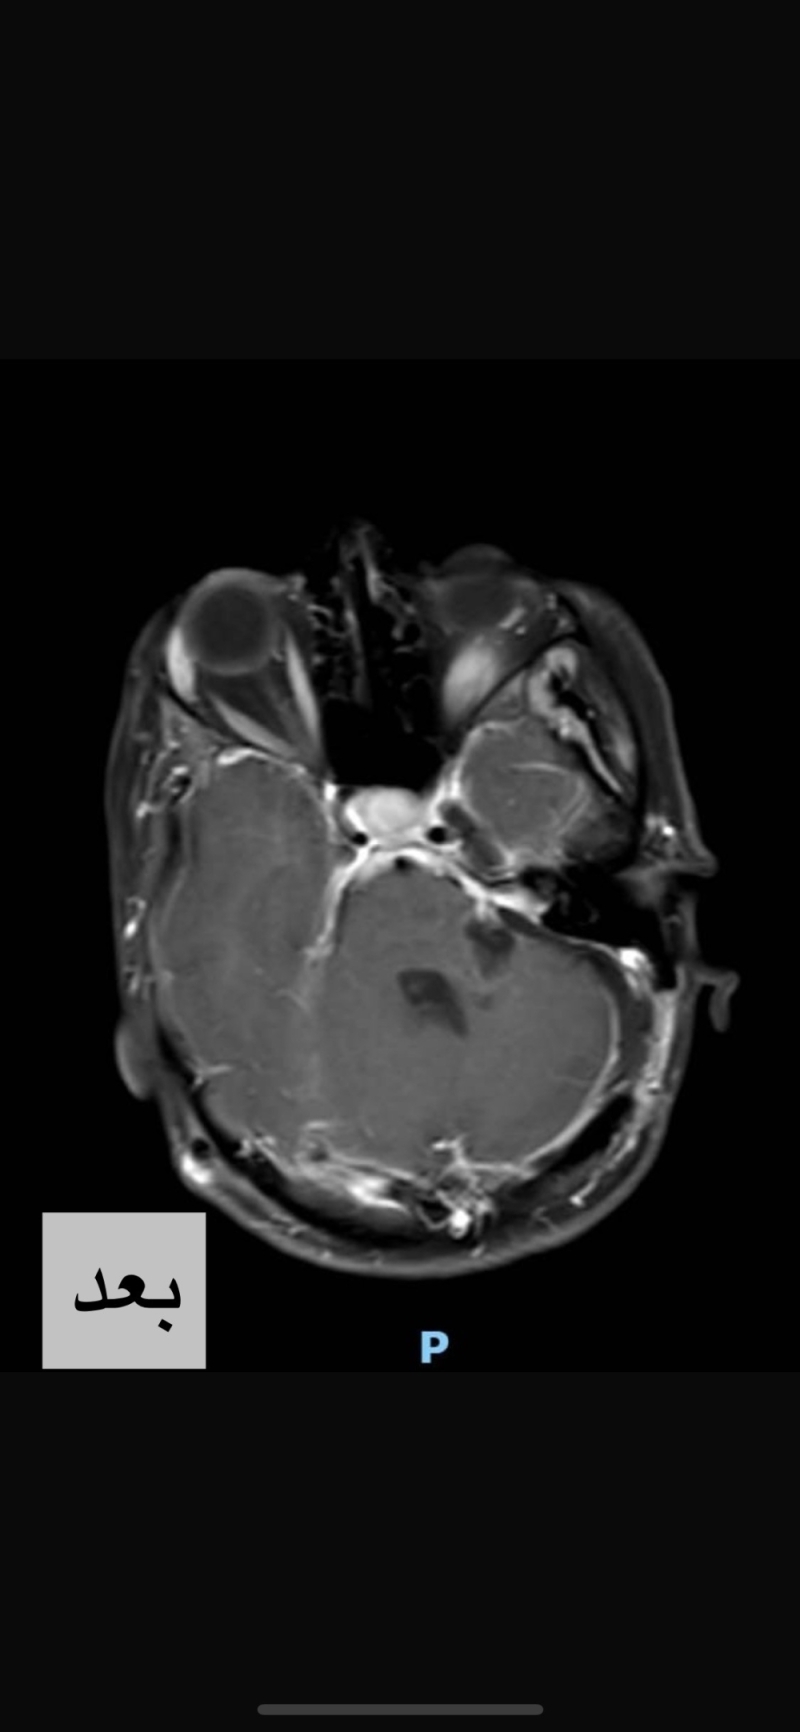

بحمدالله وتوفيقه، تمكن الفريق الطبي في مستشفى المواساة بالدمام من إجراء جراحة خطيرة ونادره لاستئصال ورم ضخم تعدى قطره ٥ سم بقاع الجمجمة بالحجرة الخلفيه للمخ.

وبإشراف الدكتور عمر الفلكي، استشاري جراحة المخ و الأعصاب، و فريقه الجراحي تم إستئصال الورم بالكامل في جراحة ميكروسكوبية دقيقة استغرقت أكثر من ١٠ ساعات تم فيها استخدام جهاز الملاح الجراحي و المراقبة المستمرة للوظائف الحركية طوال فترة الجراحة .

خضعت المريضة بعدها لعلاج طبيعي مكثف و عادت الى أسرتها و لممارست حياتها بشكل طبيعي .